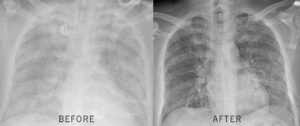

Within 17 days, the stuntman went from planning his funeral to riding 12 miles on horseback. His FEV1 jumped 31%. The rapper went from cutting sessions short to recording for hours without his inhaler. Their doctors were stunned.

My FEV1 went from 38% to 52% in just 6 weeks! My pulmonologist couldn't believe it 🙌

My wife's oxygen saturation went from 89% to 95% in 5 weeks! 👏❤️